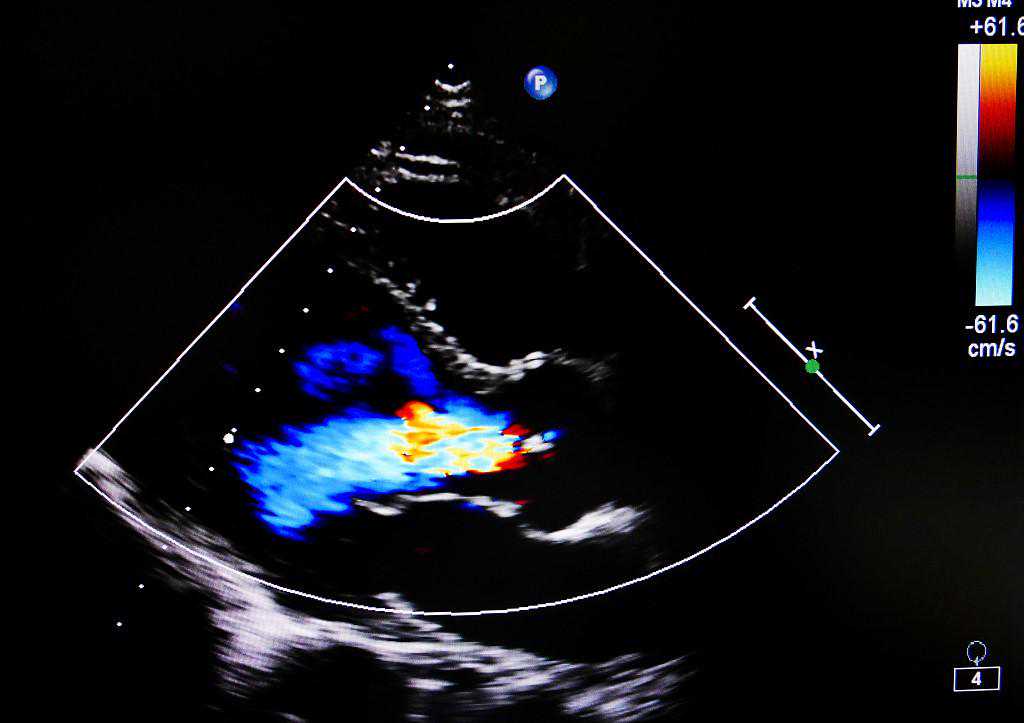

2、心脏彩超

心脏彩超是一种十分方便、有效的评估心脏状况的体检项目,它可以通过在胸壁或食道上放置一个探头,发射和接收超声波信号,然后通过计算机处理显示出心脏的图像和数据,从而来观察和测量心脏的结构和功能。心脏彩超无创,实时,经济的特点也使其成为心脏检查的首选。

那么,心脏彩超能查到什么呢?

①评估心脏的收缩和舒张功能:即射血分数(EF)和舒张功能指数(E/E’),这些指标可以反映心脏的泵血能力,以及是否存在心力衰竭或心肌缺血。及时发现和改善心功能异常可以预防心衰发作和冠心病事件。

②检测冠状动脉的血流情况、是否存在硬化或斑块:冠状动脉是供应心肌氧气、营养的重要血管,及时发现和治疗冠状动脉病变,可以预防冠心病的发生和发展。

③监测心脏的节段性室壁运动异常(RWMA):这是一种反映心肌缺血程度、范围的指标,如果某个节段的室壁运动减弱或消失,说明该节段的心肌受到了严重的缺血或坏死。及时发现和恢复节段性室壁运动异常,可以改善心肌代偿能力和预后。